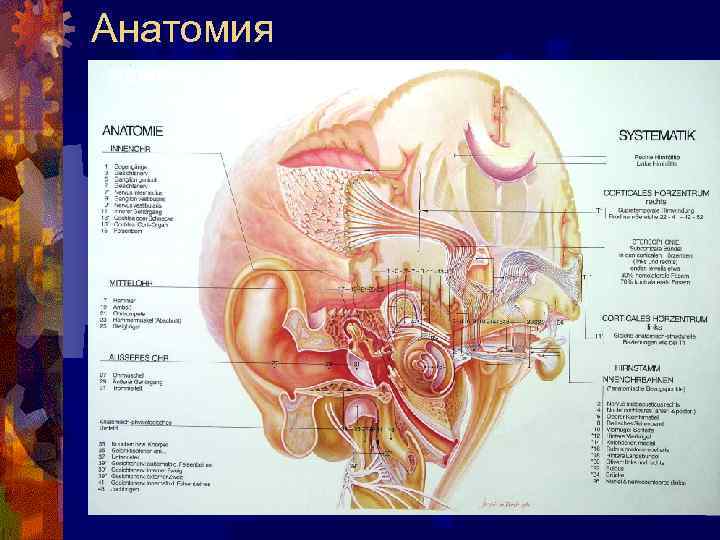

Анатомия